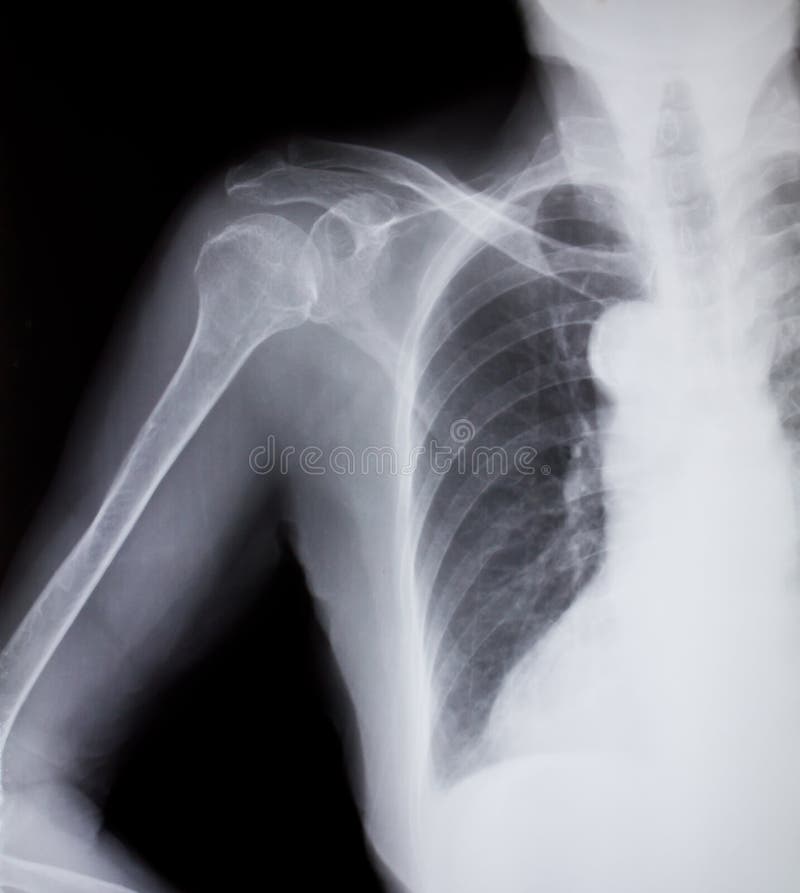

Right Arm Shoulder X Ray . Shoulder radiographs are often the only imaging exam necessary for the evaluation of acute shoulder trauma, calcific tendonitis,. Shoulder radiographs are common films to see in the emergency department, especially during the weekend after sporting. We see the glenoid or socket of the shoulder joint. Help visualize the ac joint. Shows ac joint disease and distal clavicle osteolysis. The shoulder series is fundamentally composed of two orthogonal views of the glenohumeral joint including the entire.

Fracture at Neck of Humerus ( Arm Bone ) ( Film Xray Left Shoulder and Right Arm Shoulder X Ray Shows ac joint disease and distal clavicle osteolysis. Help visualize the ac joint. Shoulder radiographs are often the only imaging exam necessary for the evaluation of acute shoulder trauma, calcific tendonitis,. We see the glenoid or socket of the shoulder joint. Shoulder radiographs are common films to see in the emergency department, especially during the weekend after sporting. The shoulder. Right Arm Shoulder X Ray.